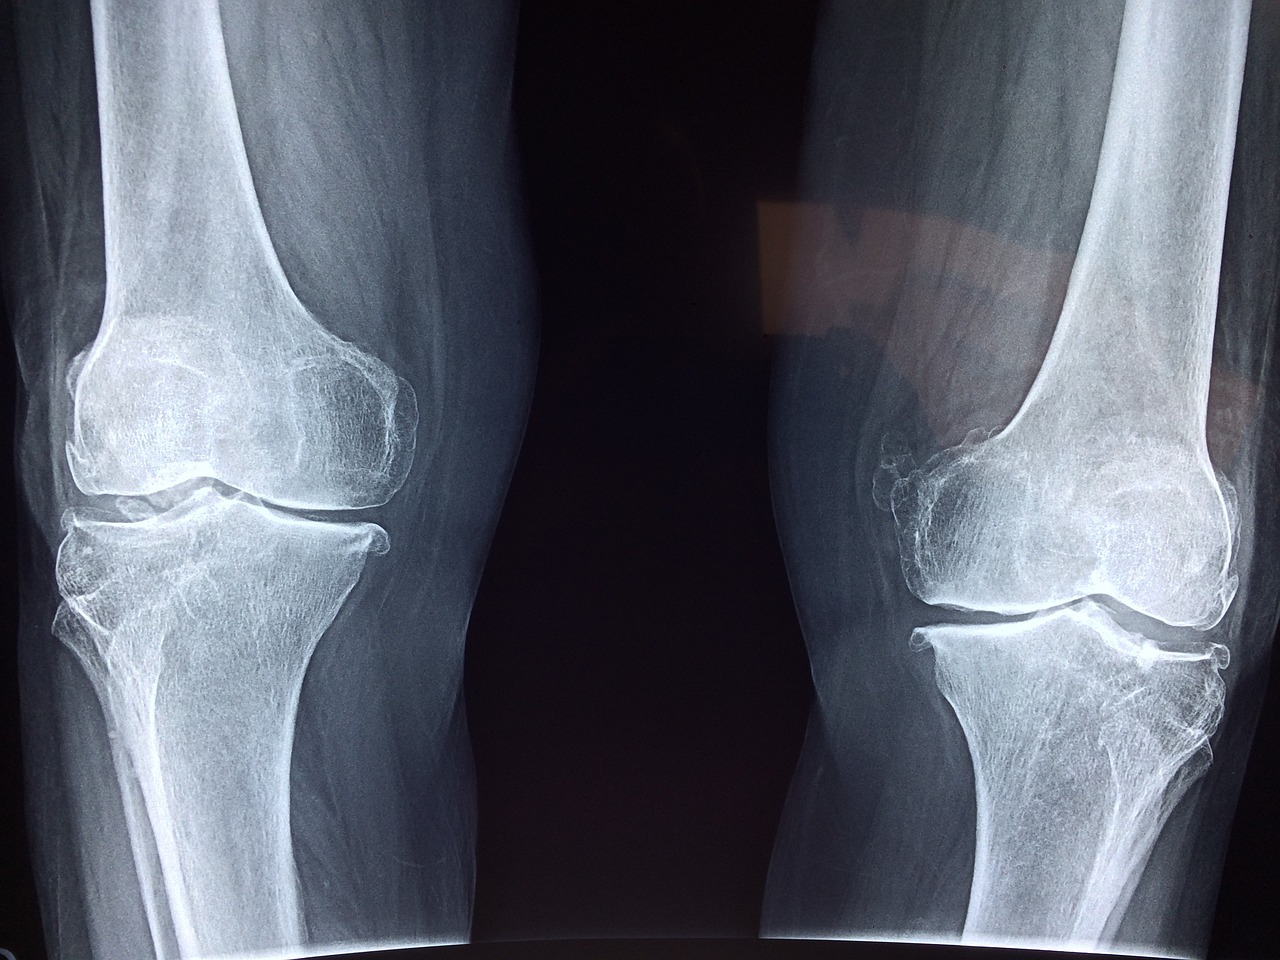

통풍은 퓨린이라는 단백질 성분이 몸 안에서 분해되면서 생기는 요산이 관절 및 주변 조직에 침착되어 염증을 일으키는 질환입니다. 주로 엄지발가락 부근에 통증이 발생하며 심한 경우 손가락, 손목, 발목 등 다른 관절에서도 발병한다고 합니다. 바람만 스쳐도 아프다고 해서 붙여진 이름이며, 대부분 40~50대 남성에게서 많이 나타납니다. 여성호르몬이 요산수치를 떨어뜨리기 때문에 주로 남성에게서 많이 나타나는 질병 중 하나입니다.

통풍은 요산 결정이 관절 내로 쌓이면서 발생하는 염증성 관절질환입니다. 통풍 초기증상은 일반적으로 갑작스럽게 발생하며, 다음과 같은 증상을 보일 수 있습니다:

- 관절 통증: 일반적으로 발작성으로 시작하며, 주로 발을 허리뼈 아래에 있는 첫 번째 발가락의 관절에서 나타납니다. 통증은 매우 강하며, 불편하거나 움직이기 어렵게 만들 수 있습니다.

- 붓기와 발작: 통풍 발작이 발생하면 관절 주위에 붓기가 생길 수 있습니다. 통증이 심한 경우 피부는 붉게 변할 수 있습니다.

- 염증: 관절 주위의 염증이 발생하여 통증, 붓기, 발적과 함께 관절이 따끔거리거나 따갑거릴 수 있습니다.